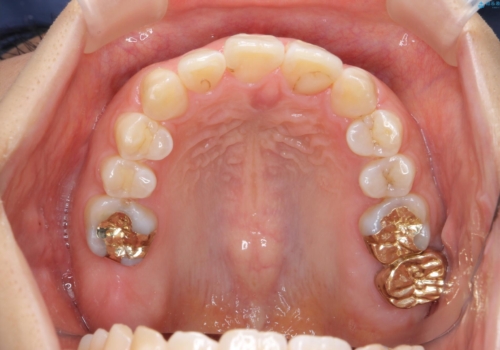

奥歯を後ろに下げて、前歯を並べています。

銀歯も白くということでしたので虫歯治療も一緒に行っています。

左上7の根の治療や左下56銀歯の治療なども行いました。

右下7は根管治療をおすすめしましたが、患者様のご希望により抜歯となり、そのスペースを利用して下の前歯をならべています。